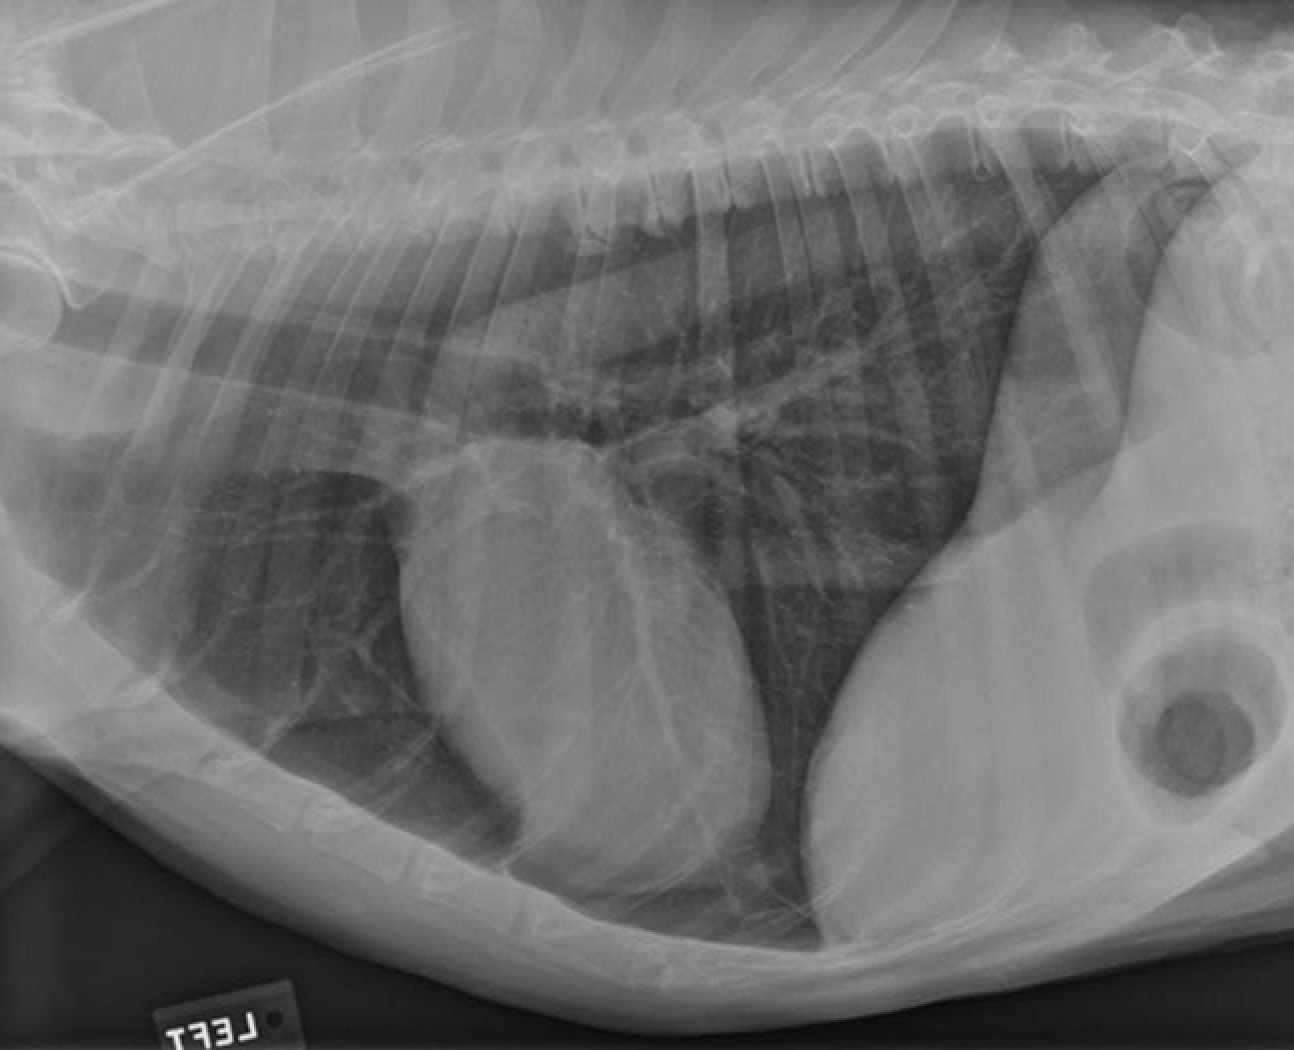

identity the structures on the thorax radiograph left lateral view

heart